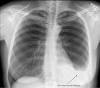

Cystic Lung Disease Presenting as Recurrent Non-traumatic Chylothorax: Case Report and a Mini-Review Chest imaging showed multiple bilateral thin-walled cysts. Thoracentesis revealed milky-colored pleural fluid, which was exudative and lymphocytic predominant. Infectious, autoimmune, and malignancy workup was negative. Vascular endothelial growth factor- ...